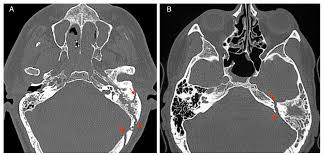

- CT scan of the head to detect the fracture and assess damage